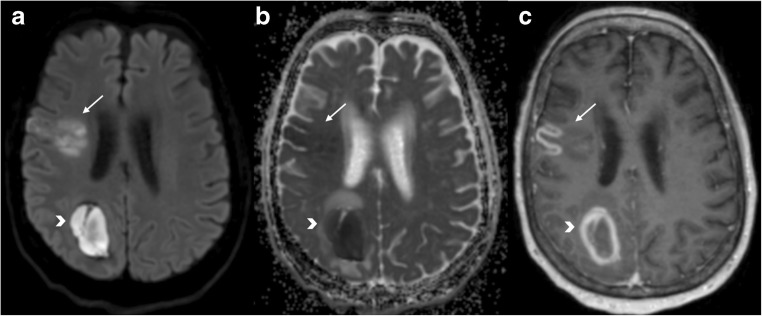

Fig. 9.

Subacute haematoma. Right parietal mass (arrowhead) showing diffusion restriction within the core on DWI and ADC maps (a and b, respectively) and a ring-enhancing pattern on T1 post gadolinium (c). This was a subacute haematoma. Clinical context is important to differentiate haemorrhage from abscess. There is also a subacute ischaemic lesion in the inferior right frontal lobe (arrows) that shows early pseudonormalisation of the ADC and gyriform enhancement post gadolinium